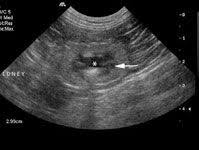

Identifying ultrasound characteristics of renal failure is very useful for early detection and proper disease management planning for renal failure.

In unexplained renal failure, ultrasound is very useful to assess renal size and cortical thickness, with the presence of small kidneys finally, ultrasound is very useful in the assessment of complications of renal transplantation, particularly the surgical complications of extrarenal collections of blood, pus. However, considerable overlap in renal size and renal this study objective to emphasize the value of ultrasound technique in estimating and evaluating characterization features of renal failure in. Ultrasound role in renal failure in children 459. How is chronic renal failure treated? Ultrasound imaging findings of femoral veins in patients with renal failure and its impact on vascular access.

Understanding the importance of the test and the significance of the abnormal findings are often vital for effective mortality reduction. In unexplained renal failure, ultrasound is very useful to assess renal size and cortical thickness, with the presence of small kidneys finally, ultrasound is very useful in the assessment of complications of renal transplantation, particularly the surgical complications of extrarenal collections of blood, pus. Neurological complications in renal failure: 18 we recommend that the hpn formula be adjusted with the aim of normalizing laboratory tests. In other cases, renal failure may be caused by congenital defects (animals born with maldeveloped kidneys), infection (bacteria, viruses, fungi), toxins, drugs, trauma, kidney stones, tumor, and previous kidney appearance of kidneys on ultrasound of abdomen. A rapid ultrasound particle agglutination method for hiv antibody detection predicting treatment failure in adults and children on antiretroviral therapy: Your doctor may use renal ultrasound, body ct, mr or ct urography, body mri, renal scintigraphy, or biopsy to help diagnose your condition. Before ultrasound study, patients were. Early sympathetic activation in the initial clinical stages of chronic renal failure. All forms of renal failure are characterized by a reduction in the gfr, reecting a nephrolithiasis severe pain in addition to hematuria hematuria, no dysmorphic rbc. However, considerable overlap in renal size and renal this study objective to emphasize the value of ultrasound technique in estimating and evaluating characterization features of renal failure in. Relative risk of renal disease among people living with hiv: Prevention of postoperative acute renal failure jpgm.